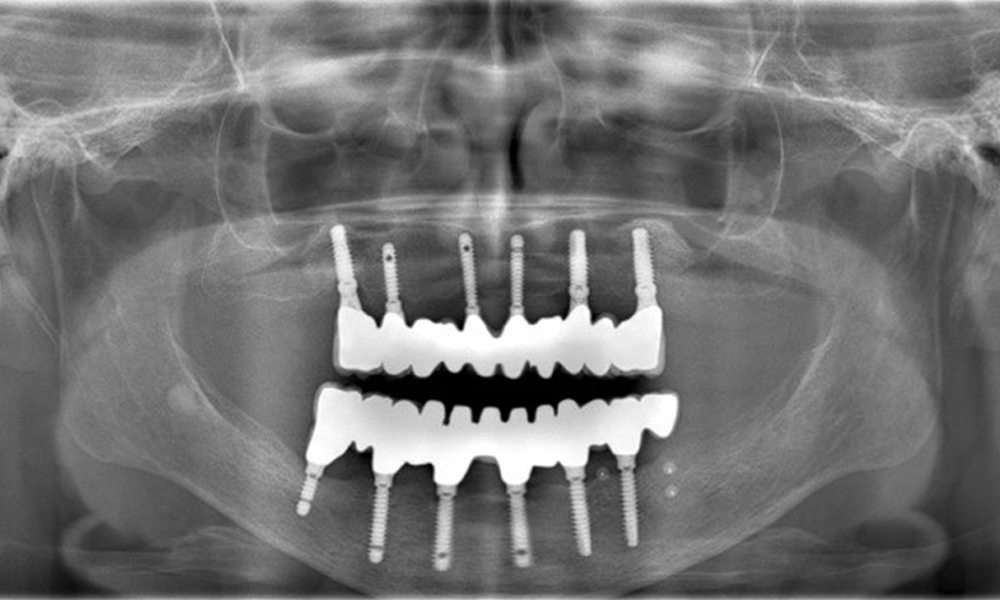

Рентгенографските изображения показват костна резорбция.

Фигура 2: Рентгенографските изображения показват костна резорбция.

Възстановявания: импланти в области 011, 013, 015, 021, 023, 025, 031, 033, 035, 042, 044, 046

Употребата на Lixiana представлява рисков фактор, поради което рискът от усложнения се счита за умерен. Оралното здраве е стабилно и добро. За ранно откриване на потенциален периимплантит, по време на контролните прегледи трябва да се измерва дълбочината на сондиране (PD). Ако има увеличение на PD при имплантата в сравнение с изходното ниво, съчетано с дифузно кървене, трябва да се продължи с рентгенова диагностика (напр. зъбни рентгенови снимки).